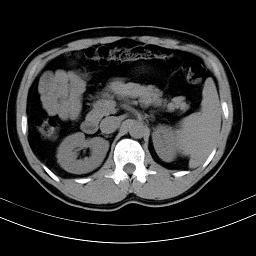

标题: CT18388:肝脏膈肌间隙内大量脂肪密度影 [打印本页]

标题: CT18388:肝脏膈肌间隙内大量脂肪密度影

腹腔脂肪沉积过多

腹腔脂肪沉积症

激素治疗的病人容易脂肪沉积